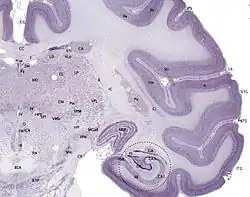

Cresyl violet stain

It is used in biology and medicine as a histological stain. Cresyl violet is an effective and reliable stain used for light microscopy sections. Initially, tissue sections are "defatted" by passing through graded dilutions of ethanol. Then, rehydrated by passing back through decreasing concentrations of ethanol. Lastly, back into water. The ethanol solutions act to differentiate the stain, causing myelin and other components to lose color whereas perikarya retain the color. It is also used to find Helicobacter pylori.[1]

Cresyl violet is used to stain Heinz bodies in red blood corpuscles or for staining of the neurons in the brain and spinal cord. It is used to demonstrate the Nissl substance in the neurons and cell nuclei. In this role it is also often used as a counterstain to Luxol fast blue, which stains the myelin.